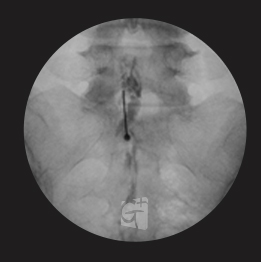

요추 신경성형술

-

꼬리뼈 구멍으로 카테타 삽입

-

척추관 안쪽으로 진입 약물 주입

-

원인부위 염증 제거 및 유착 박리

-

유착박리로 추간공 확보, 신경 압박 감소

-

척추관에서 약물이 잘 퍼져나오는 모습

-

허리 신경 전체를 효과적으로 치료